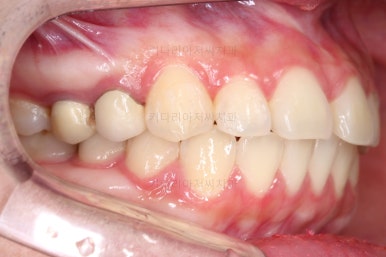

치아 갯수 및 사이즈 문제로 위아래의 정중선은 100% 일치시키긴 힘들지만 가능한 선에서 최대한 맞추었고요.

윗니가 1개 없는 상태에서의 교합도 잘 맞추고 마무리를 했습니다.

다시 틈새가 벌어지지 말라고 유지철사를 붙여주었고요.

물론 약간 다시 벌어질 수는 있으나 그 정도는 처음에 비하면 아무 문제도 아닌 정도죠.